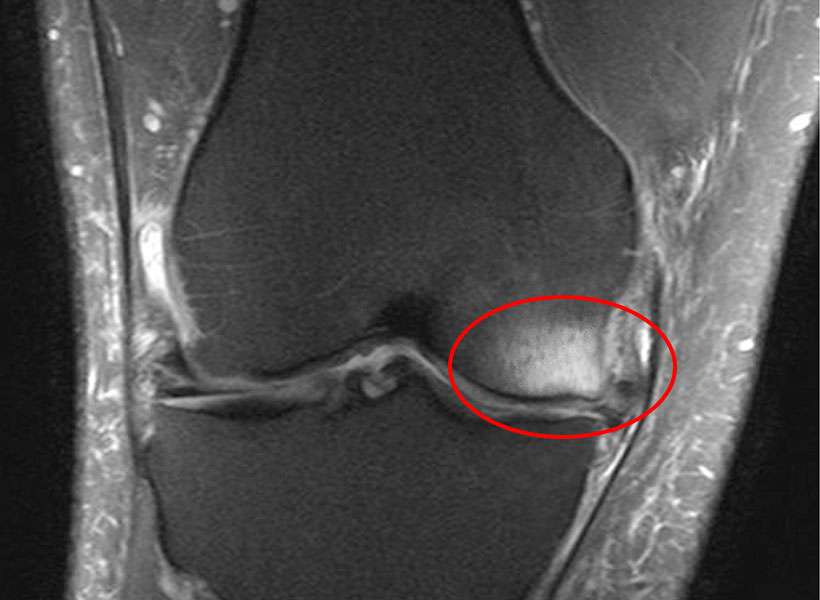

Bone marrow lesions are areas within the bone that appear as signal changes on MRI, typically beneath the cartilage surface of the knee joint. They are sometimes referred to as bone marrow edema–like lesions, though they represent a variety of underlying bone changes rather than simple fluid accumulation.

They are not visible on standard X-rays and are best identified using MRI.

- MRI of the knee to identify bone marrow lesions and associated joint changes